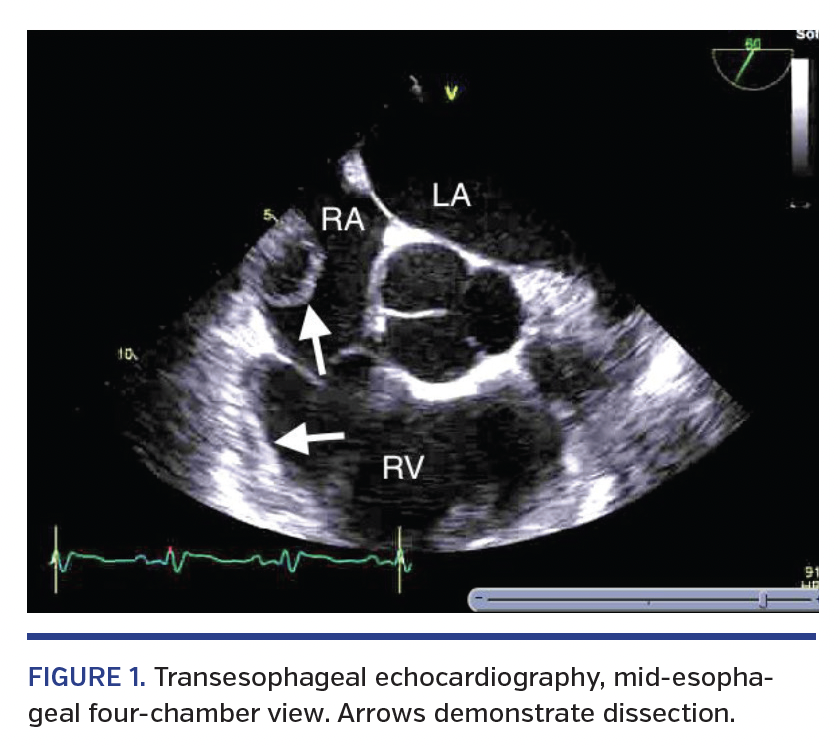

A 62-year-old male with an abnormal stress test underwent stent placement of the left anterior descending coronary artery. Soon after, this was complicated by stent thrombosis leading to cardiogenic shock that was refractory to pressors, requiring intra-aortic balloon placement. The patient was eventually weaned off pressors and ventilatory support, but developed septic shock secondary to hospital-acquired pneumonia, and shortly thereafter developed cardiogenic shock. A Swan-Ganz catheter was then placed with the aide of an Arrow Spring-Wire guide (Teleflex), marked 0.035˝ diameter x 17-3/4˝ with an Arrow Advancer (Teleflex). The patient remained hemodynamically stable throughout the procedure. Transesophageal echocardiography was then performed after placement to rule out any cardiogenic abnormalities contributing to the presentation. Results demonstrated a right atrial dissection with extension into the superior vena cava and right ventricle not seen on previous echocardiographic findings (Figures 1 and 2). No intervention was performed as the patient’s hemodynamic status improved. We propose that during Swan-Ganz catheter placement, the guidewire sheared the intimal lining of the superior vena cava and endocardium.